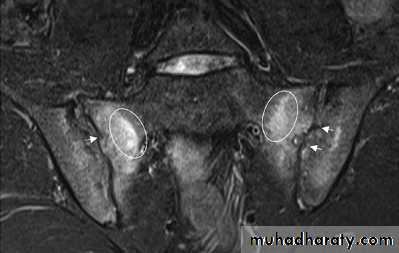

Patients with early disease can have normal Xrays, and if clinical suspicion is high, MRI should be performed. This is much more sensitive for detection of early sacroiliitis than Xray and can also detect inflammatory changes in the lumbar spine.

MRI and ultrasound with power Doppler are increasingly employed to detect synovial inflammation and inflammation at the entheses.